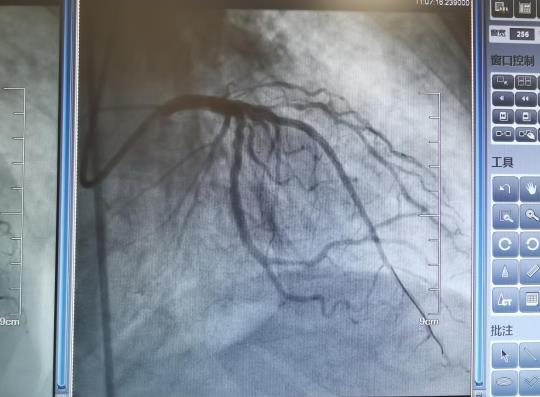

经过急诊室及时有效的救治,王老症状暂时有所缓解,但此时并未脱离危险。患者曾经有过心梗、支架术史,这又再次发生了急性心梗,并且伴有慢性心衰、慢性肾衰,病情危重。心血管内科康丽娜主任医师当机立断,将患者收住院。康丽娜主任医师决定在三级防护下给患者进行冠状动脉造影检查及介入治疗,术后血滤,在缓解王老病痛的同时,最大程度减轻造影剂对肾脏的损害。

康丽娜主任医师介绍,急性心梗介入治疗是一项高风险手术,要求术者有高超的技术和应变力。即使在平时,空调手术间内,穿着几十斤重的铅衣,也经常汗如雨下。更何况疫情期间,除了铅衣之外,还要裹上密不透气的防护服,戴上双层口罩、双层手套,这不仅是对手术人员身体素质的极大挑战,同时也是对手术医生技术的严格考验。

麻醉手术室接到手术通知后,在傅双护士长带领下按照三级防护规范充分准备。最终,凭借精湛的技术和高度的责任感,康丽娜主任医师带着助手李冠男医师,在护士王梅红和技师丁伟的默契配合下,顺利完成了冠脉造影检查,并且给王老进行了介入治疗。随着两枚支架的顺利植入,王老的血管又重新获得了充足的血液灌注。一场手术下来,大家全身湿透,但是,看着王老痛楚的眉眼舒展开来,大家都露出欣慰的笑容。术后,重症监护病房陈显成医师及护理团队及时给王老进行了血滤治疗。